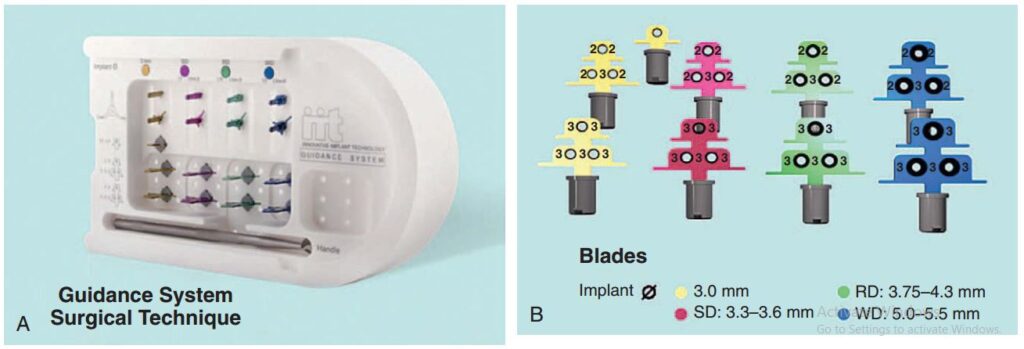

Dụng cụ hướng dẫn định vị Implant

Giúp xác định đúng vị trí đặt Implant và lựa chọn đường kính Implant tối ưu nhất (H2.18). Bộ hướng dẫn ITT gồm có:

– Tấm Titan, giúp hướng dẫn đường kính và vị trí của 1 – 2 Implant.

– Pin đo đạc có phần mở rộng, giúp hướng dẫn đường kính và vị trí Implant ở bệnh nhân không răng.

– Pin song song, để xác định độ song song của Implant.

– Cán của tấm Titan, giúp cầm nắm và đặt tấm Titan vào trong miệng 1 cách an toàn.